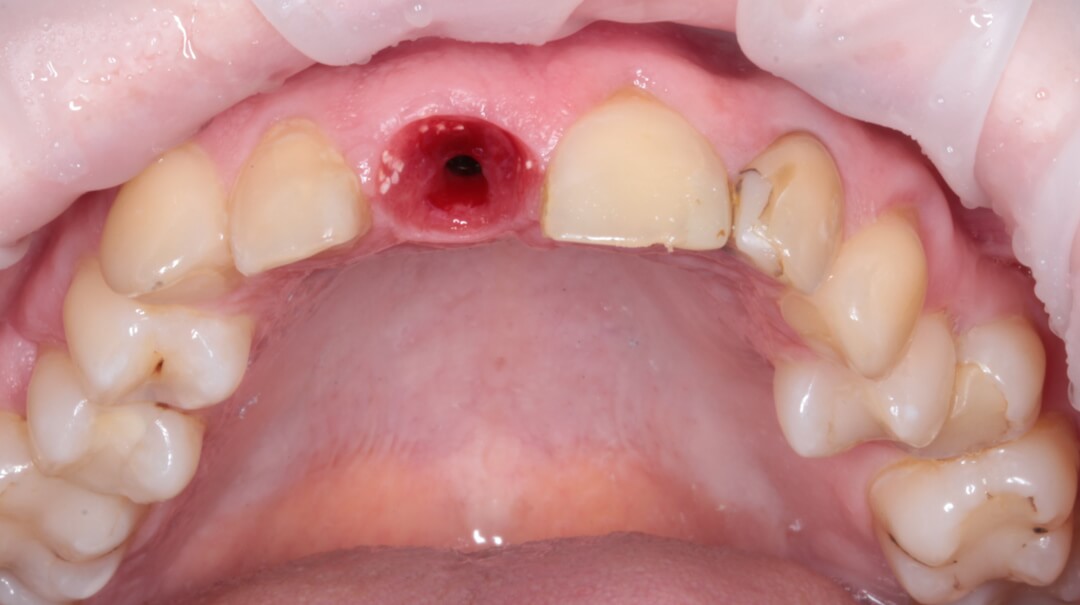

Пациентка в возрасте 49 лет обратилась в клинику для консультации. Ее интересовала возможность улучшить эстетический вид передней группы зубов верхней челюсти. У нее 11-ый зуб был травмирован около 20 лет тому назад. В результате на рентгенограмме диагностирован перелом корня и этот зуб не подлежал повторному восстановлению.

Рис. 1 Исходная ситуация.